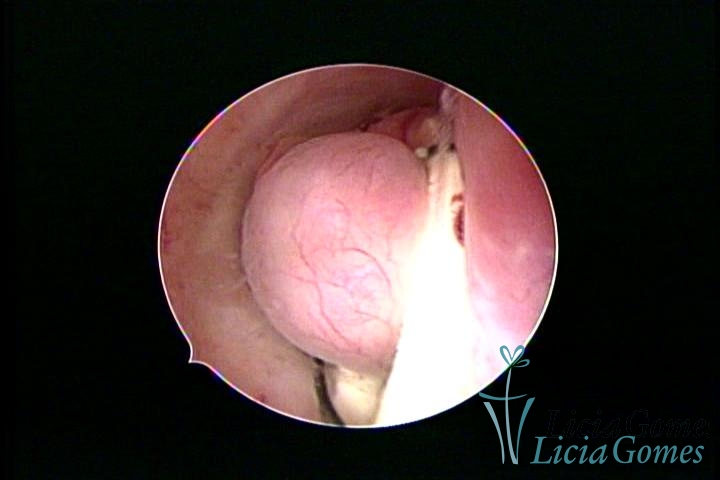

Uterine cavity with IUD and accumulated light mucus